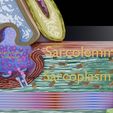

神经肌肉接头示意图

/https://fbi.cults3d.com/uploaders/27147996/illustration-file/c849c3e7-5bf4-40eb-b9fe-a92c2e324d1b/8669.jpg)